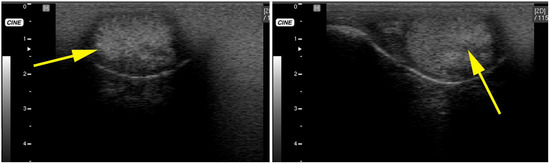

- ultrasonography